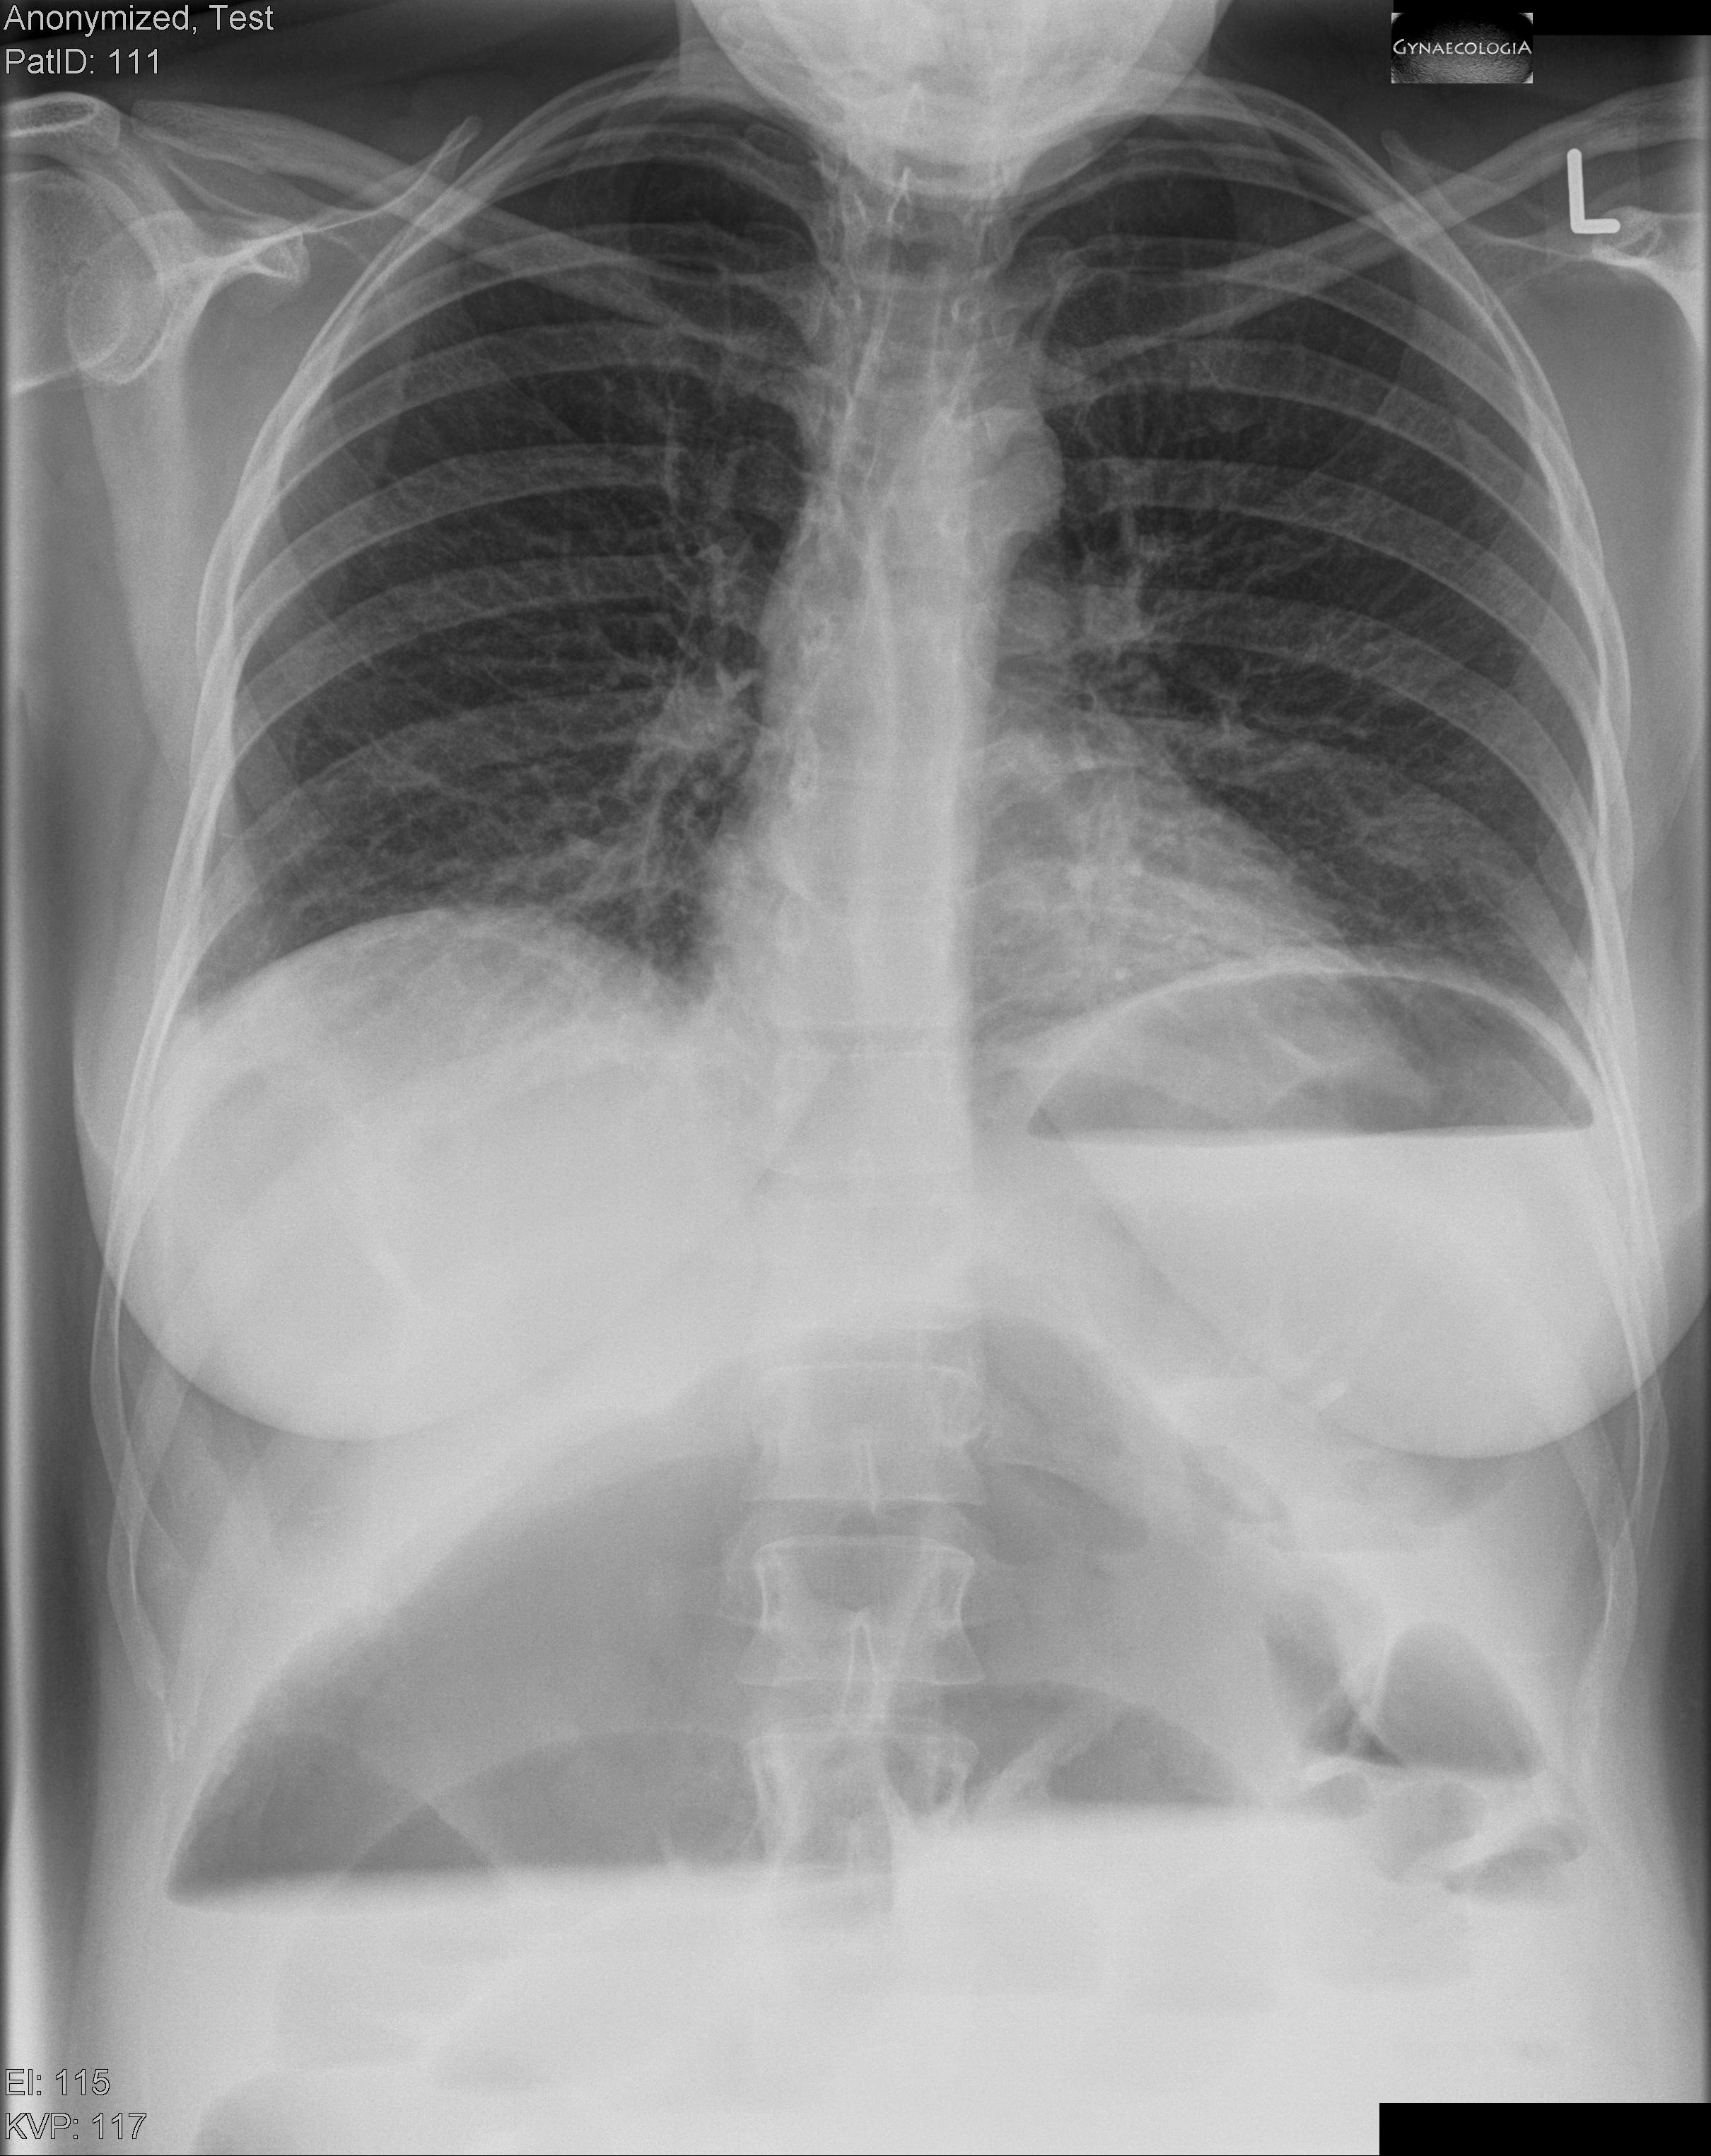

A 36-year-old 2 gravida 1 para in the 36th week of pregnancy presented with abdominal distension, acute epigastric pain, vomiting and constipation. A significant leucocytosis was noted. The patient had a previous cesarean section as well as previous bowel surgery. The fetus showed no abnormality and was age-appropriate. Premature uterine contractions were excluded. After consulting with the general surgeons and ragiologists a thorax x-ray was performed.

The diagnosis of volvulus was made. The treatment consisted of a laparotomy via a midline vertical incision, cesarean section followed by right hemicolectomy. The patient recovered quickly and the preterm neonate was discharched just a few days later.

Volvulus in pregnancy is a rare but serious complication associated with significant maternal and fetal morbidity and even mortality. Diagnosis is usually delayed and complications include perforation, peritonitis, sepsis, preterm delivery and intrauterine fetal demise. Volvulus is reported to be responsible for as high as 25% of cases of acute intestinal obstruction during pregnancy and puerperium. The classic clinical triad involves abdominal pain, distention and constipation. Diagnosis can be established mainly due to clinical suspicion, in difficult cases even with an x-ray or, preferably, with sonography (whirlpool sign).